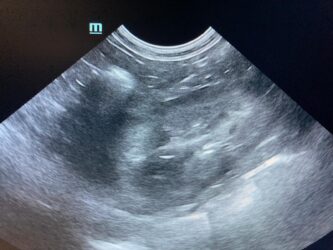

Dimitri, CV, 9.6kg, 11j, MC, bijgeruis 4/6 waarvoor hij vetmedin krijgt en opgevolgd wordt door cardioloog:

21/08/2025: Bij buurtcollega aangeboden voor hematurie. Plast vlot, op’t einde bloed te zien. Mevr. kookt zelf voor hem. Echo gehad + UOZ (geen idee hoe dit werd gecollecteerd) gedaan. Veel bloed in de…